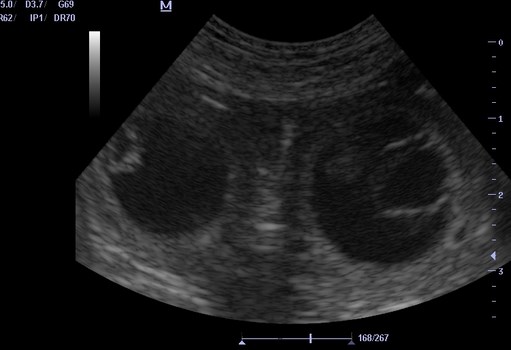

+++ Erste Bilder unserer Beaglebaby's - Ultraschall: +++

Bereits vor dem Ultraschall waren erste Anzeichen für die

Trächtigkeit zu erkennen:

Nadja 25. - 27. Trächtigkeits-Tag%20(Kopie).jpg)

+++ Halbzeit - Trächtigkeit +++

Die Hälfte der Tragzeit ist geschafft - Nadja genießt -

so schön kann "schwanger" sein !!! Nadja 30. - 33. Trächtigkeits-Tag:%20(Kopie).jpg)

31. Tag: Die Ausbildung der Organe ist abgeschlossen.

Die Föten sehen nun wie Hunde aus. Rumpf und Kopf sind unterscheidbar.

Fellfarbe entwickelt sich. Das Geschlecht ist zu bestimmen.

Der Herzschlag der Föten ist per Ultraschall sichtbar - per Stethoskop hörbar.![]()